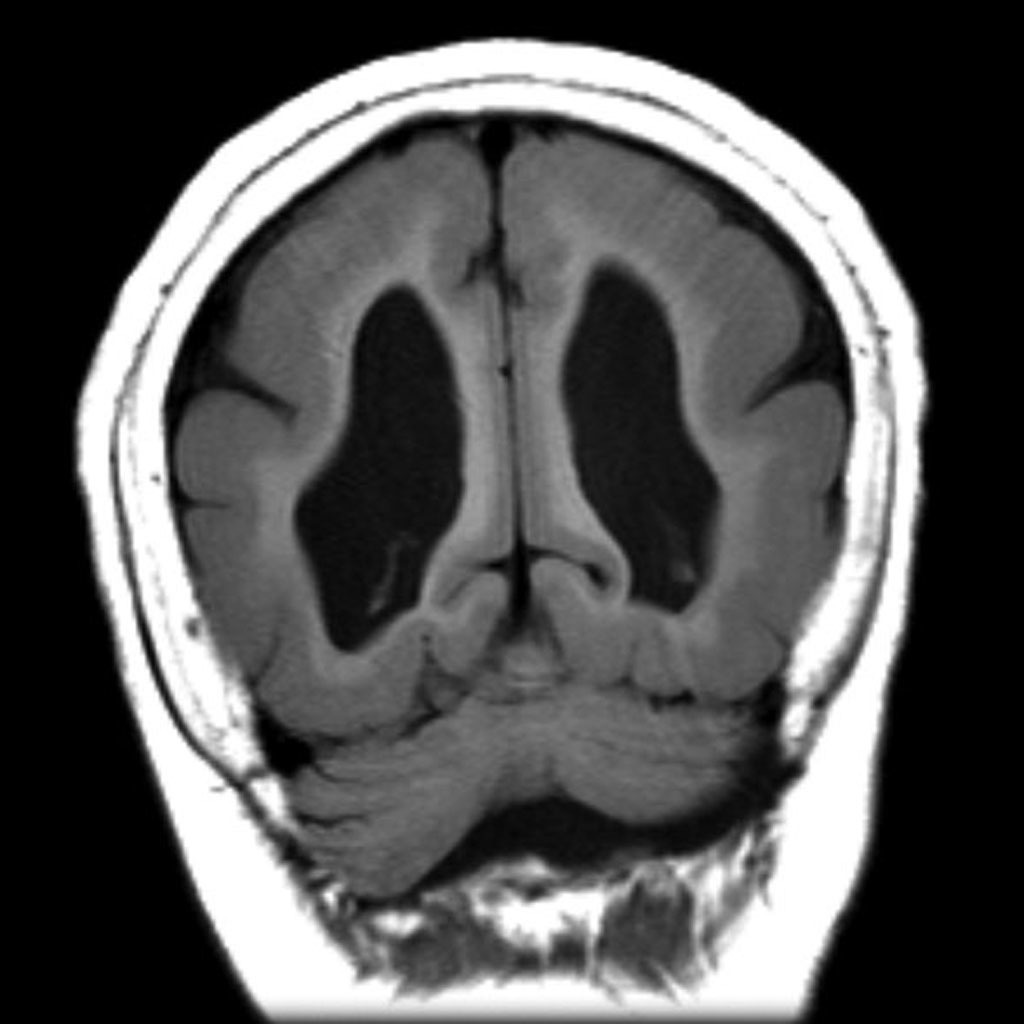

Polymicrogyria

Characterized by numerous small gyri

Due to interference in neuronal migration